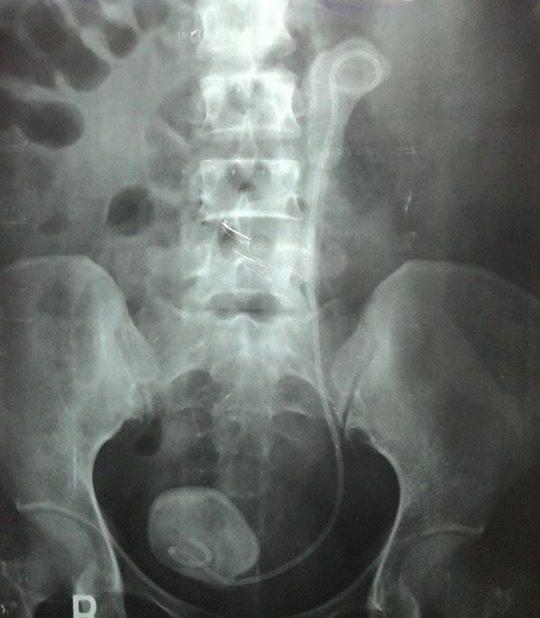

Ngày 30/6, BS Phan Văn Hoàng, khoa Cấp cứu BV Bình Dân, cho biết khoa đang điều trị trường hợp bệnh nhân nữ T.T.H (46 tuổi, quê ở Kiên Giang) bị thận trái nhiễm trùng, ứ nước do ống thông JJ bỏ quên trong ổ bụng.

Một tháng trước, bà H. đã đến cấp cứu tại BV Bình Dân. Qua chẩn đoán hình ảnh, bác sĩ phát hiện trong ổ bụng bà H. có một chiếc ống thông JJ một đầu trong thận và một đầu trong bàng quang bị nhiễm trùng và bám sỏi rất nhiều. Ống thông JJ một loại ống thông bằng nhựa dẻo mềm được đặt vào trong niệu quản khi phẫu thuật hay khi nội soi, thông thường sau khi tán sỏi bệnh nhân phải tái khám để bác sĩ rút ống ra.